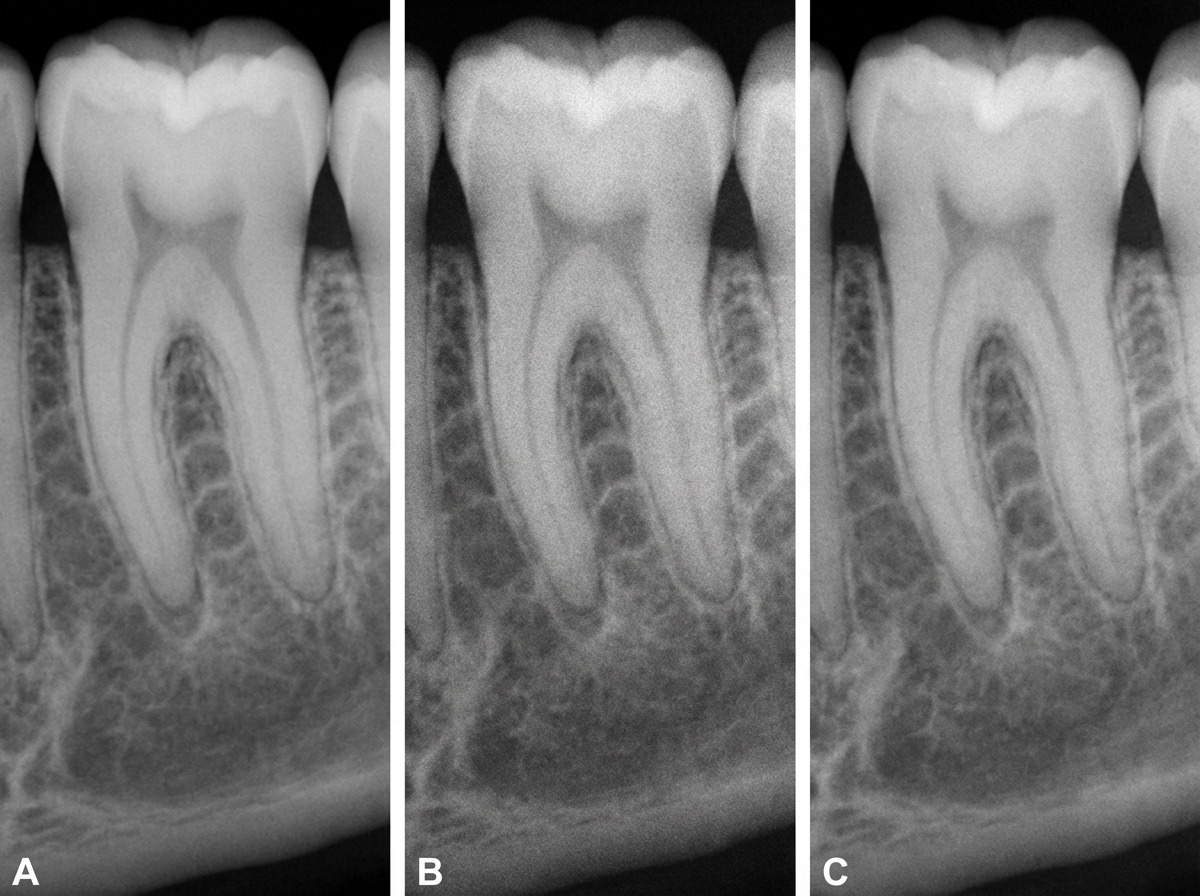

Three radiographs of the same tooth were taken using a digital intra-oral X-ray system, an intensifying screen/film cassette combination, and conventional dental film (F speed). Which of the following X-rays was taken with conventional dental film?

Explanation: ***Radiograph C*** - **Conventional F-speed dental film** produces characteristic **coarse grain structure** and higher **image noise** compared to digital systems. - Shows **lower contrast resolution** and requires **higher radiation dose** to achieve adequate image density. *Radiograph A* - **Digital intraoral sensors** produce the **sharpest image quality** with excellent **spatial resolution** and minimal noise. - Offers **immediate image acquisition** with **lower radiation dose** requirements compared to conventional film. *Radiograph B* - **Intensifying screen/film cassette** systems show **intermediate image quality** with some **blur** due to **phosphor light scattering**. - Demonstrates **better contrast** than conventional film but **less spatial resolution** than digital systems. *All of the above* - Only **one radiograph** can be taken with conventional dental film, making this option logically incorrect. - Each imaging system produces **distinct image characteristics** that allow differentiation between the three modalities.